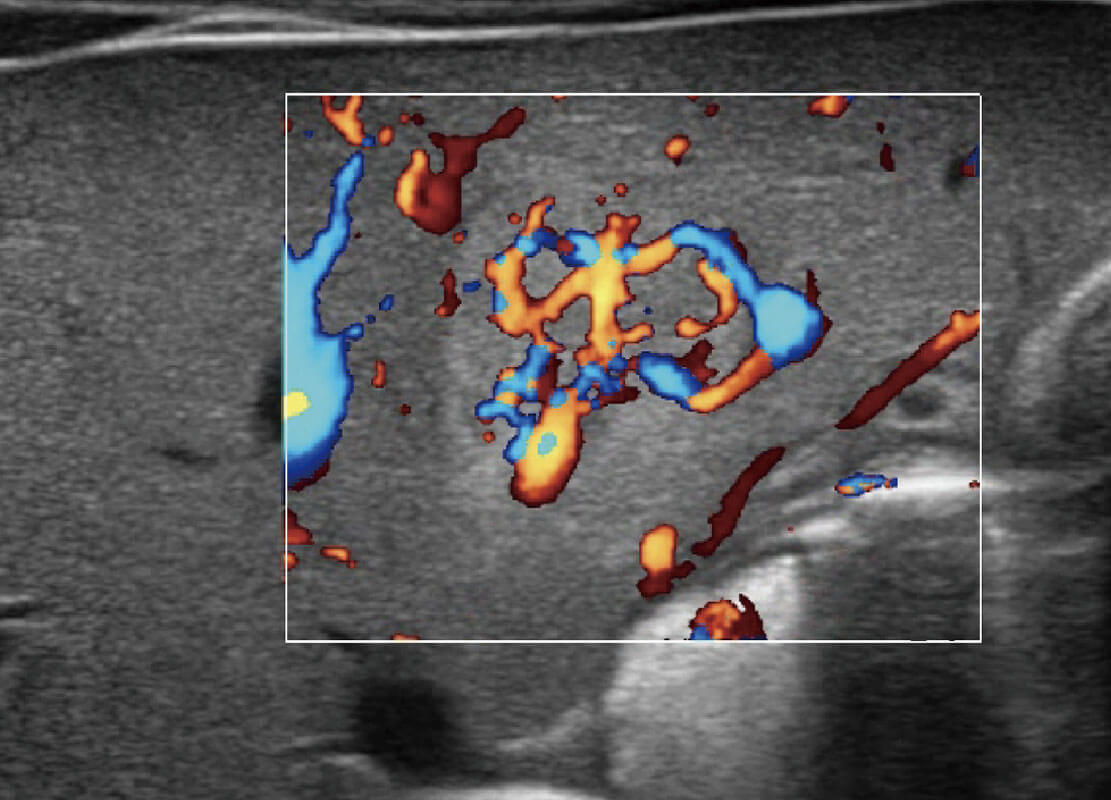

P60搭載寬頻帶線陣探頭、寬景成像、彈性成像技術(shù),為您提供乳腺應(yīng)用方案。P60支持高頻相控陣探頭、線陣探頭、腹部高頻探頭、腹部微凸探頭等,豐富的探頭群搭載敏感的彩色血流成像,適用于新生兒多種臟器檢測(cè)要求,滿足新生兒篩查需求。

乳腺癌顯微血流